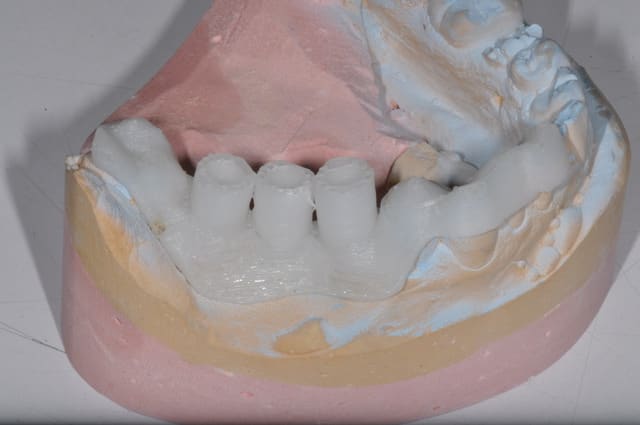

Le cas de ce matin, cela montre que même avec une planif et un guide c'est le temps opératoire qui décide

j'ai bêtement cassé la table vesti de la 45 lors de l'exo

par sécurité je suis allé chercher un meilleur ancrage en distal,

Donc le guide ne fait pas tout!!!